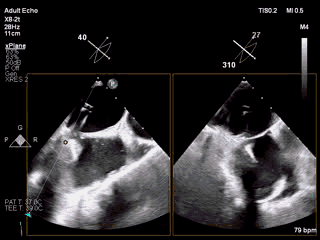

视频2 经食道超声心动图引导穿刺房间隔

4月11日上午患者在全麻下接受MitraClip经皮二尖瓣夹合术。术中穿刺右股静脉,经食道超声心动图(TEE)再次评估瓣膜病变(视频1),并引导顺利穿刺房间隔(视频2)。随后送入二尖瓣夹合系统,在TEE引导下于二尖瓣P2区植入MitraClip XTR夹合器一枚(视频3),二尖瓣关闭不全减轻,但夹合器内侧仍存在反流(视频4)。团队决定为患者植入第二枚夹合器(MitraClip NTR),手术过程顺利(视频5)。TEE三维显示在植入第二枚NTR夹合器后,二尖瓣呈双孔启闭,两枚夹合器位置、结构正常(视频6)。配备心腔镜功能的TEE三维TrueVue彩色多普勒显示二尖瓣反流将至少量(视频7),且未致二尖瓣口狭窄(图1),夹合效果满意。手术通过视频连线得到香港亚洲心脏病中心主任林逸贤教授的技术支持。